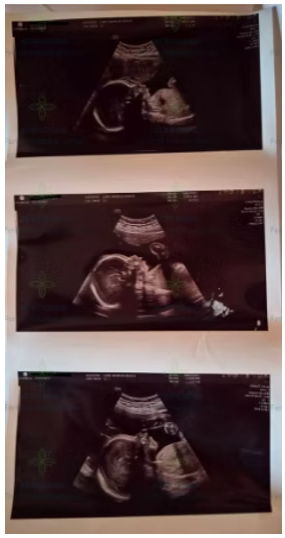

ACRC Global の別の代理母は、先日、妊娠24週の定期健診を無事に終えました。妊娠における大切な節目のひとつです。超音波検査では赤ちゃんの顔がはっきりと映し出され、代理母と依頼者の双方にとって、期待と喜びに満ちた瞬間となりました。

妊娠24週の健診は、妊娠中期において特に重要な検査のひとつで、詳細な胎児スクリーニング(先天異常の確認)、血糖検査、そして母体全体の健康評価が含まれます。これらの検査により、妊娠後期に向けて、代理母と赤ちゃんの双方が良好な状態であることが確認されます。